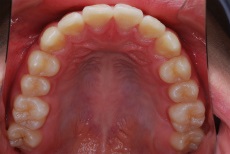

写真で確認できますように上あごの左右側12才臼歯がきちんと生えています。この噛み合わせに至るまで、本症例では固定式矯正装置での本格的矯正治療はせずにI期治療のみで終了しています。